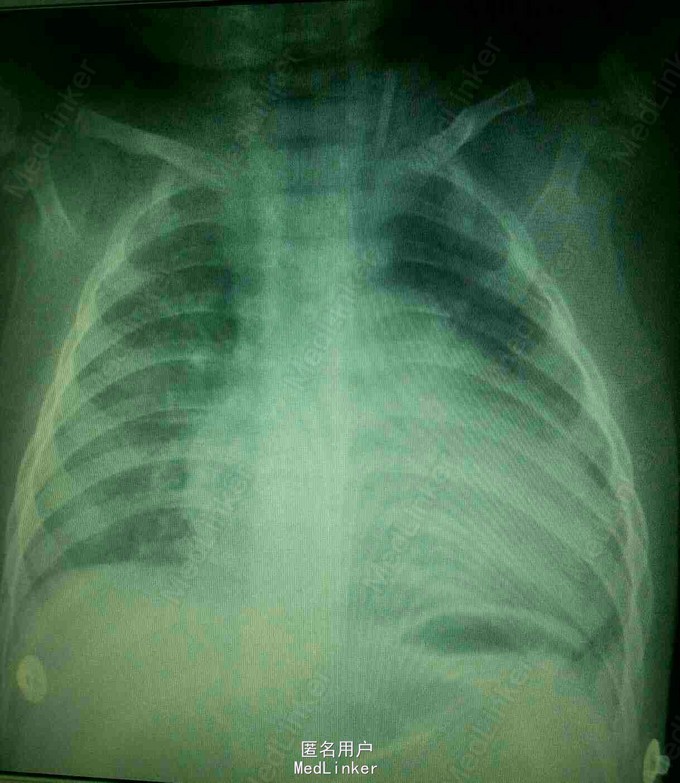

患儿女,9月14天。因咳嗽4月余,加重伴气促、呼吸困难2月入院。

双肺呼吸音粗,可闻及中量哮鸣音及湿罗音。腹部彭隆,肝脾未触及。辅查:B超提示ASD,PDA,三尖瓣轻度反流,肺动脉高压(中度)。血象高,以淋巴为主。